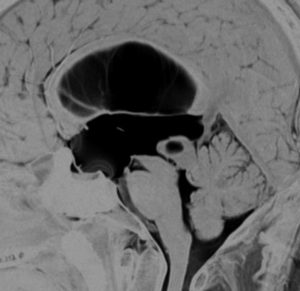

19歳で偶然見つかった例

頭部打撲で検査され偶然発見された19歳男性ものです。中脳視蓋全体が腫大して腫瘍化しています。左側にのう胞があり周囲が淡くガドリニウムで増強されます。

中脳水道の癒着閉塞により,高度の停止性水頭症になっています。高身長ですが頭囲が61cmありました。小さい頃から頭が大きいので家族も気にならないようです。数年以上あるいは10年近くの長期にわたってこの水頭症は変わらないのでしょう。

頭痛などの症状はなく,眼底所見も視神経乳頭の異常はありませんでした。無治療で経過観察をしています。認知機能も全く正常で,国立大学から大学院に進む予定です。